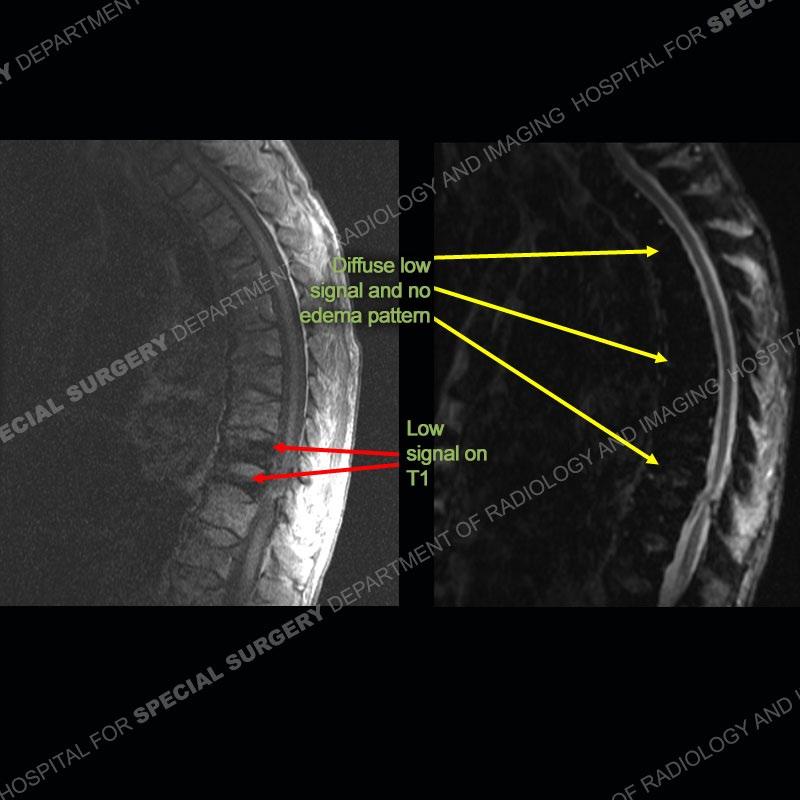

Radiographs of the thoracic and later lumbar spine demonstrate osteoporosis and a wedge compression deformity of at least one lower thoracic vertebrae. On the MRI, the T1 images demonstrate marked low signal of two lower thoracic vertebrae. On the IR sequence, there is diffuse low signal of the bone without any areas of marrow edema pattern. The subsequent bone scan demonstrates increased radiotracer uptake of the two lower thoracic vertebrae. Of important note on the coronal T2 images, there is markedly low signal of the liver and spleen.

This case demonstrates particularly the effect of the iron on the MR imaging. To a certain degree, the T1 and T2 signal of the bone is somewhat decreased but especially the IR signal of the bone is markedly decreased.

Although not well discussed in the literature, when blood product or iron is deposited in the bone, on IR sequences there is a marked low signal of the bone. It can be so much so that even when a fracture is present, no edema pattern can be seen. In this case, the marked low signal of the lower thoracic vertebrae on T1 corresponds to fractures which show increased uptake on the bone scan but no edema pattern on the IR image. This case highlights that simply utilizing the signal on the MRI is not enough. Both morphometry and signal must be utilized and on all pulse sequences to appreciate the pathology.